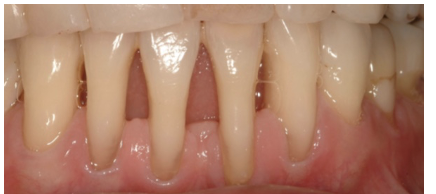

20

Q

what is this

A

necrotising gingivitis

21

necrotising periodontitis